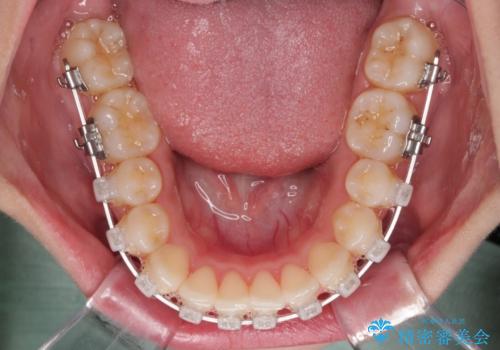

- クリアブラケット

- 上下前歯のデコボコを気にして来院された患者様です。

上顎歯列が下顎の歯列に対して狭小であり、一部下顎の奥歯が上顎よりも外側に位置している状態でした。

上顎の急速拡大装置を使用して上顎骨を側方に拡大することで上顎歯列を拡大し、下顎歯列も拡大できるようにすることで、歯列を整えることとしました。

歯列矯正では基本的に骨格を改善することはできませんが、急速拡大装置(MARPE)を使用することで上顎骨を側方に拡大させることができ、咬合状態を大きく改善することができます。